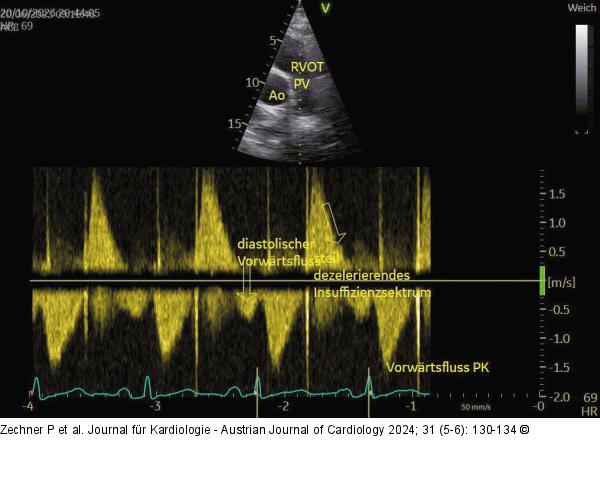

Abbildung 3: Echo Gleicher Patient wie in Abb. 1+2; parasternale kurze Achse mit CW-Doppler über der PK. Die schwere PI erkennt man am steil dezelerierenden Insuffizienzspektrum (schräger Pfeil nach unten), sodass der Rückfluss bereits in der Mitte der Diastole aufhört. Der spätdiastolische Vorwärtsfluss nach der P-Welle (Pfeil nach unten) zeigt den Druckausgleich zwischen Pulmonalis und Ventrikel bereits in der späten Systole an. |

Gleicher Patient wie in Abb. 1+2; parasternale kurze Achse mit CW-Doppler über der PK. Die schwere PI erkennt man am steil dezelerierenden Insuffizienzspektrum (schräger Pfeil nach unten), sodass der Rückfluss bereits in der Mitte der Diastole aufhört. Der spätdiastolische Vorwärtsfluss nach der P-Welle (Pfeil nach unten) zeigt den Druckausgleich zwischen Pulmonalis und Ventrikel bereits in der späten Systole an. |